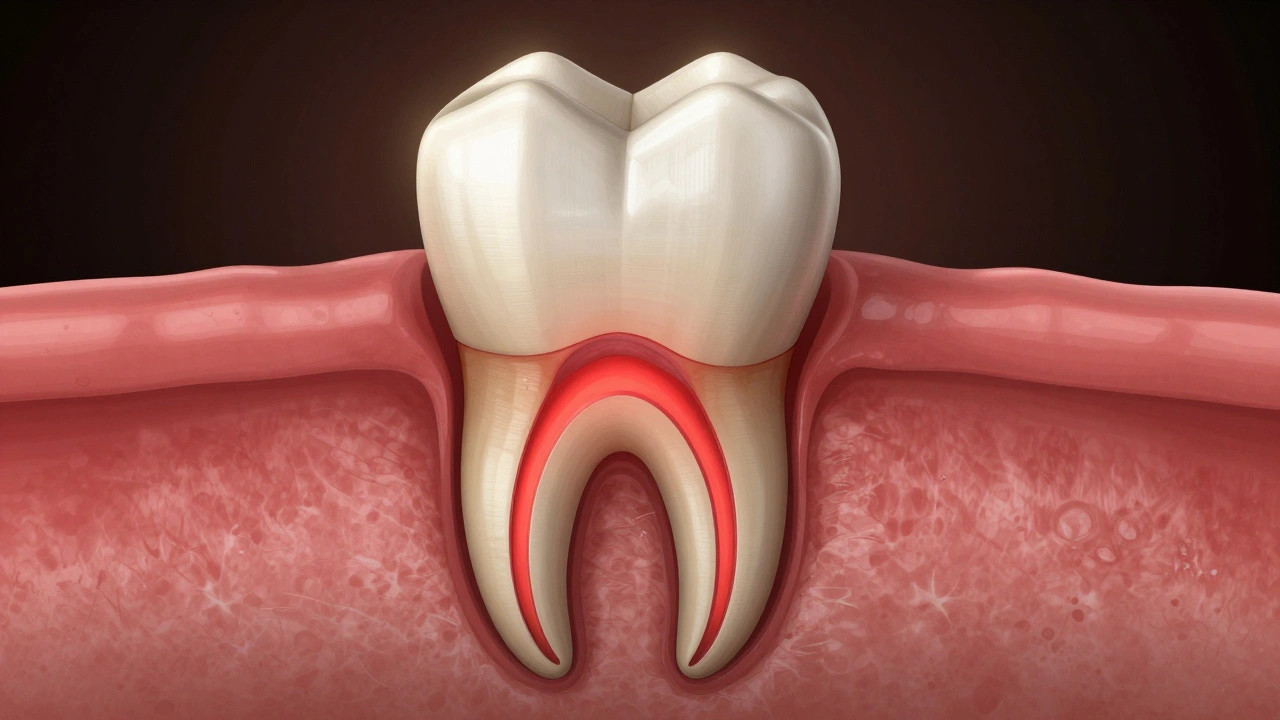

Ošetření kořenových kanálků není jen „vyčištění“ zubu. Je to operace, při které se odstraňuje zánětlivá nebo mrtvá tkáň z nitra zubu - tzv. pulpová tkáň. Při tomto procesu se zub mechanicky upravuje, očišťuje a plní. I když je nerv odstraněn, kolem kořene zubu zůstává tkáň - kost, dásně, vazivo. A ta může být po ošetření zánětlivá, otoklá, citlivá.

Bolest není způsobená tím, že „zůstal nerv“, ale tím, že tělo reaguje na zásah. Je to stejné jako když si po operaci zubu odstraníte - může to bolet i několik dní. Tělo potřebuje čas, aby se zahojilo.

Průřez zubu s zánětlivými tkáněmi kolem kořene a poškozenou kostí.